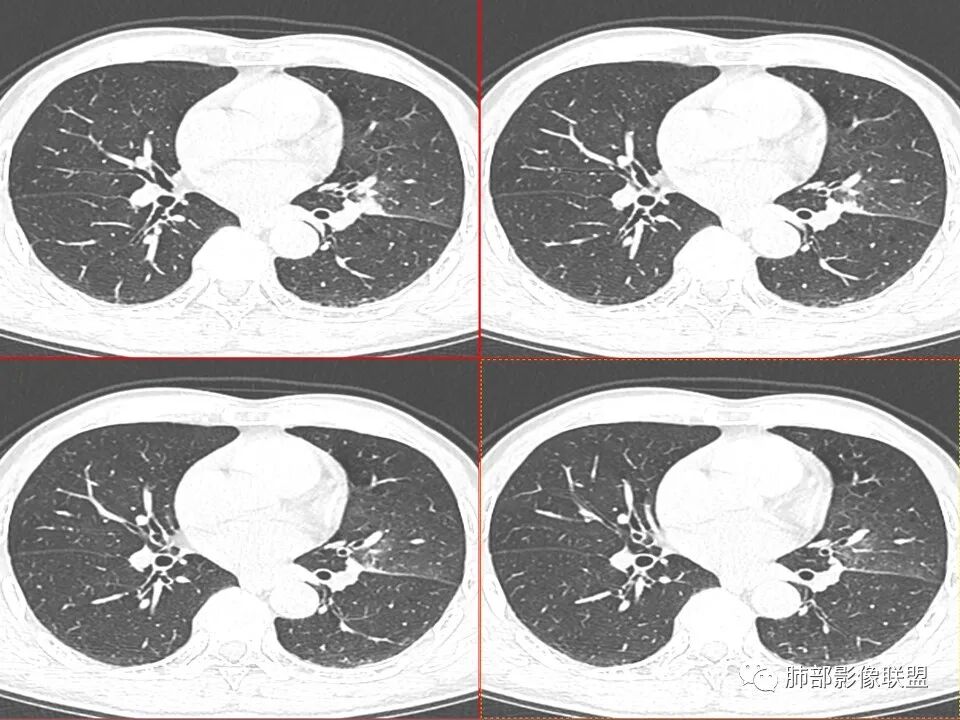

左肺上叶舌段近肺门区不规则结节,密度较均匀,结节边缘平直为主,可见粗短毛刺、毛刺偏软,浅分叶,收缩力不强,膨隆也不明显,周围可见模糊GGO,病灶内部支气管显示不清,病变远端支气管明显扩张,病灶与叶间裂呈宽基底相连,见刀切征,并见叶间裂多发结节影,叶间裂未见明显移位。

患者推测中老年人,无明显临床症状,肺气肿背景不明显,虽然病灶整体炎性征象较多,叶间胸膜多发结节,常规要考虑结核和腺癌,PET-CT肿瘤和炎性病变都可以高摄取,敏感性高,但特异性不高,而且腺癌周围缺乏清晰的磨玻璃及收缩力不强,故暂不考虑;虽然左肺上叶舌段病灶与支气管关系密切,如果周围磨玻璃推测为早期的阻塞性炎症,还有CYFR轻度升高,鳞癌不能除外,但是病灶的整体形态比较符合炎性改变。本病例可惜未行CT增强扫描,无法观察结节的强化特点及病灶内血管走行情况。